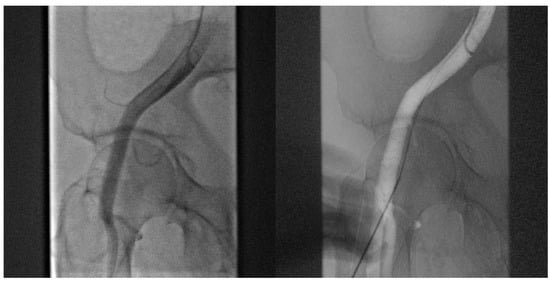

- Angiography-guided femoral puncture: A secondary access is necessary (radial or femoral) for the possibility of reaching the proximal part of the CFA to perform digital subtraction angiography (DSA) and road mapping Figure 3 to guide the puncture.

Figure 3. DSA allow to puncture in the correct site of CFA avoiding bifurcation and other small vessels.

- Cardiogenic shock pre-PPCI: Time is muscle. After basal coronary angiography, in order to place a pMCS the use of DSA would probably be the faster option Figure 8.